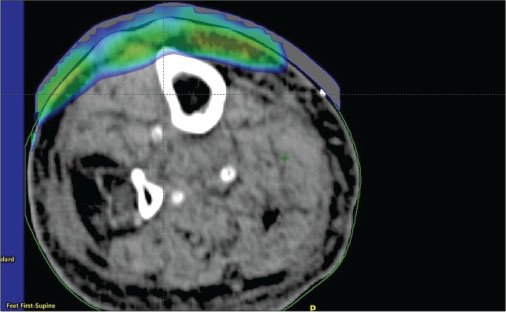

He was commenced on external beam RT (EBRT). We selected electron beam therapy as the cutaneous lesions were mostly superficial (involving the dermis and deep dermis). CT-based RT simulation was done in the supine position with left leg abducted and slightly externally rotated to keep the contralateral leg away from the electron beam. Thin axial sections CT images were acquired after intravenous contrast injection from mid-thigh to foot. Images were transferred to treatment planning system, and three-dimensional reconstruction was done. A single enface portal with 6 MeV, energy electron beam, was selected ensuring adequate coverage of the affected skin. A tissue-equivalent bolus of 5-mm thickness was also kept over the skin to deliver adequate dose to the skin lesions. Dosimetric plan evaluation with different parameters was done ensuring adequate coverage of the targets [Figure 4] and [5]. He received a total dose of 33 Gy in 11 daily fractions over 13 days. He tolerated the treatment without significant acute RT toxicity. On follow-up after 6 weeks, complete regressions of the lesions were observed without any late RT toxicity except mild hyperpigmentations over the affected area.

|?Figure. 4? Axial view

|?Figure. 5? Sagittal view